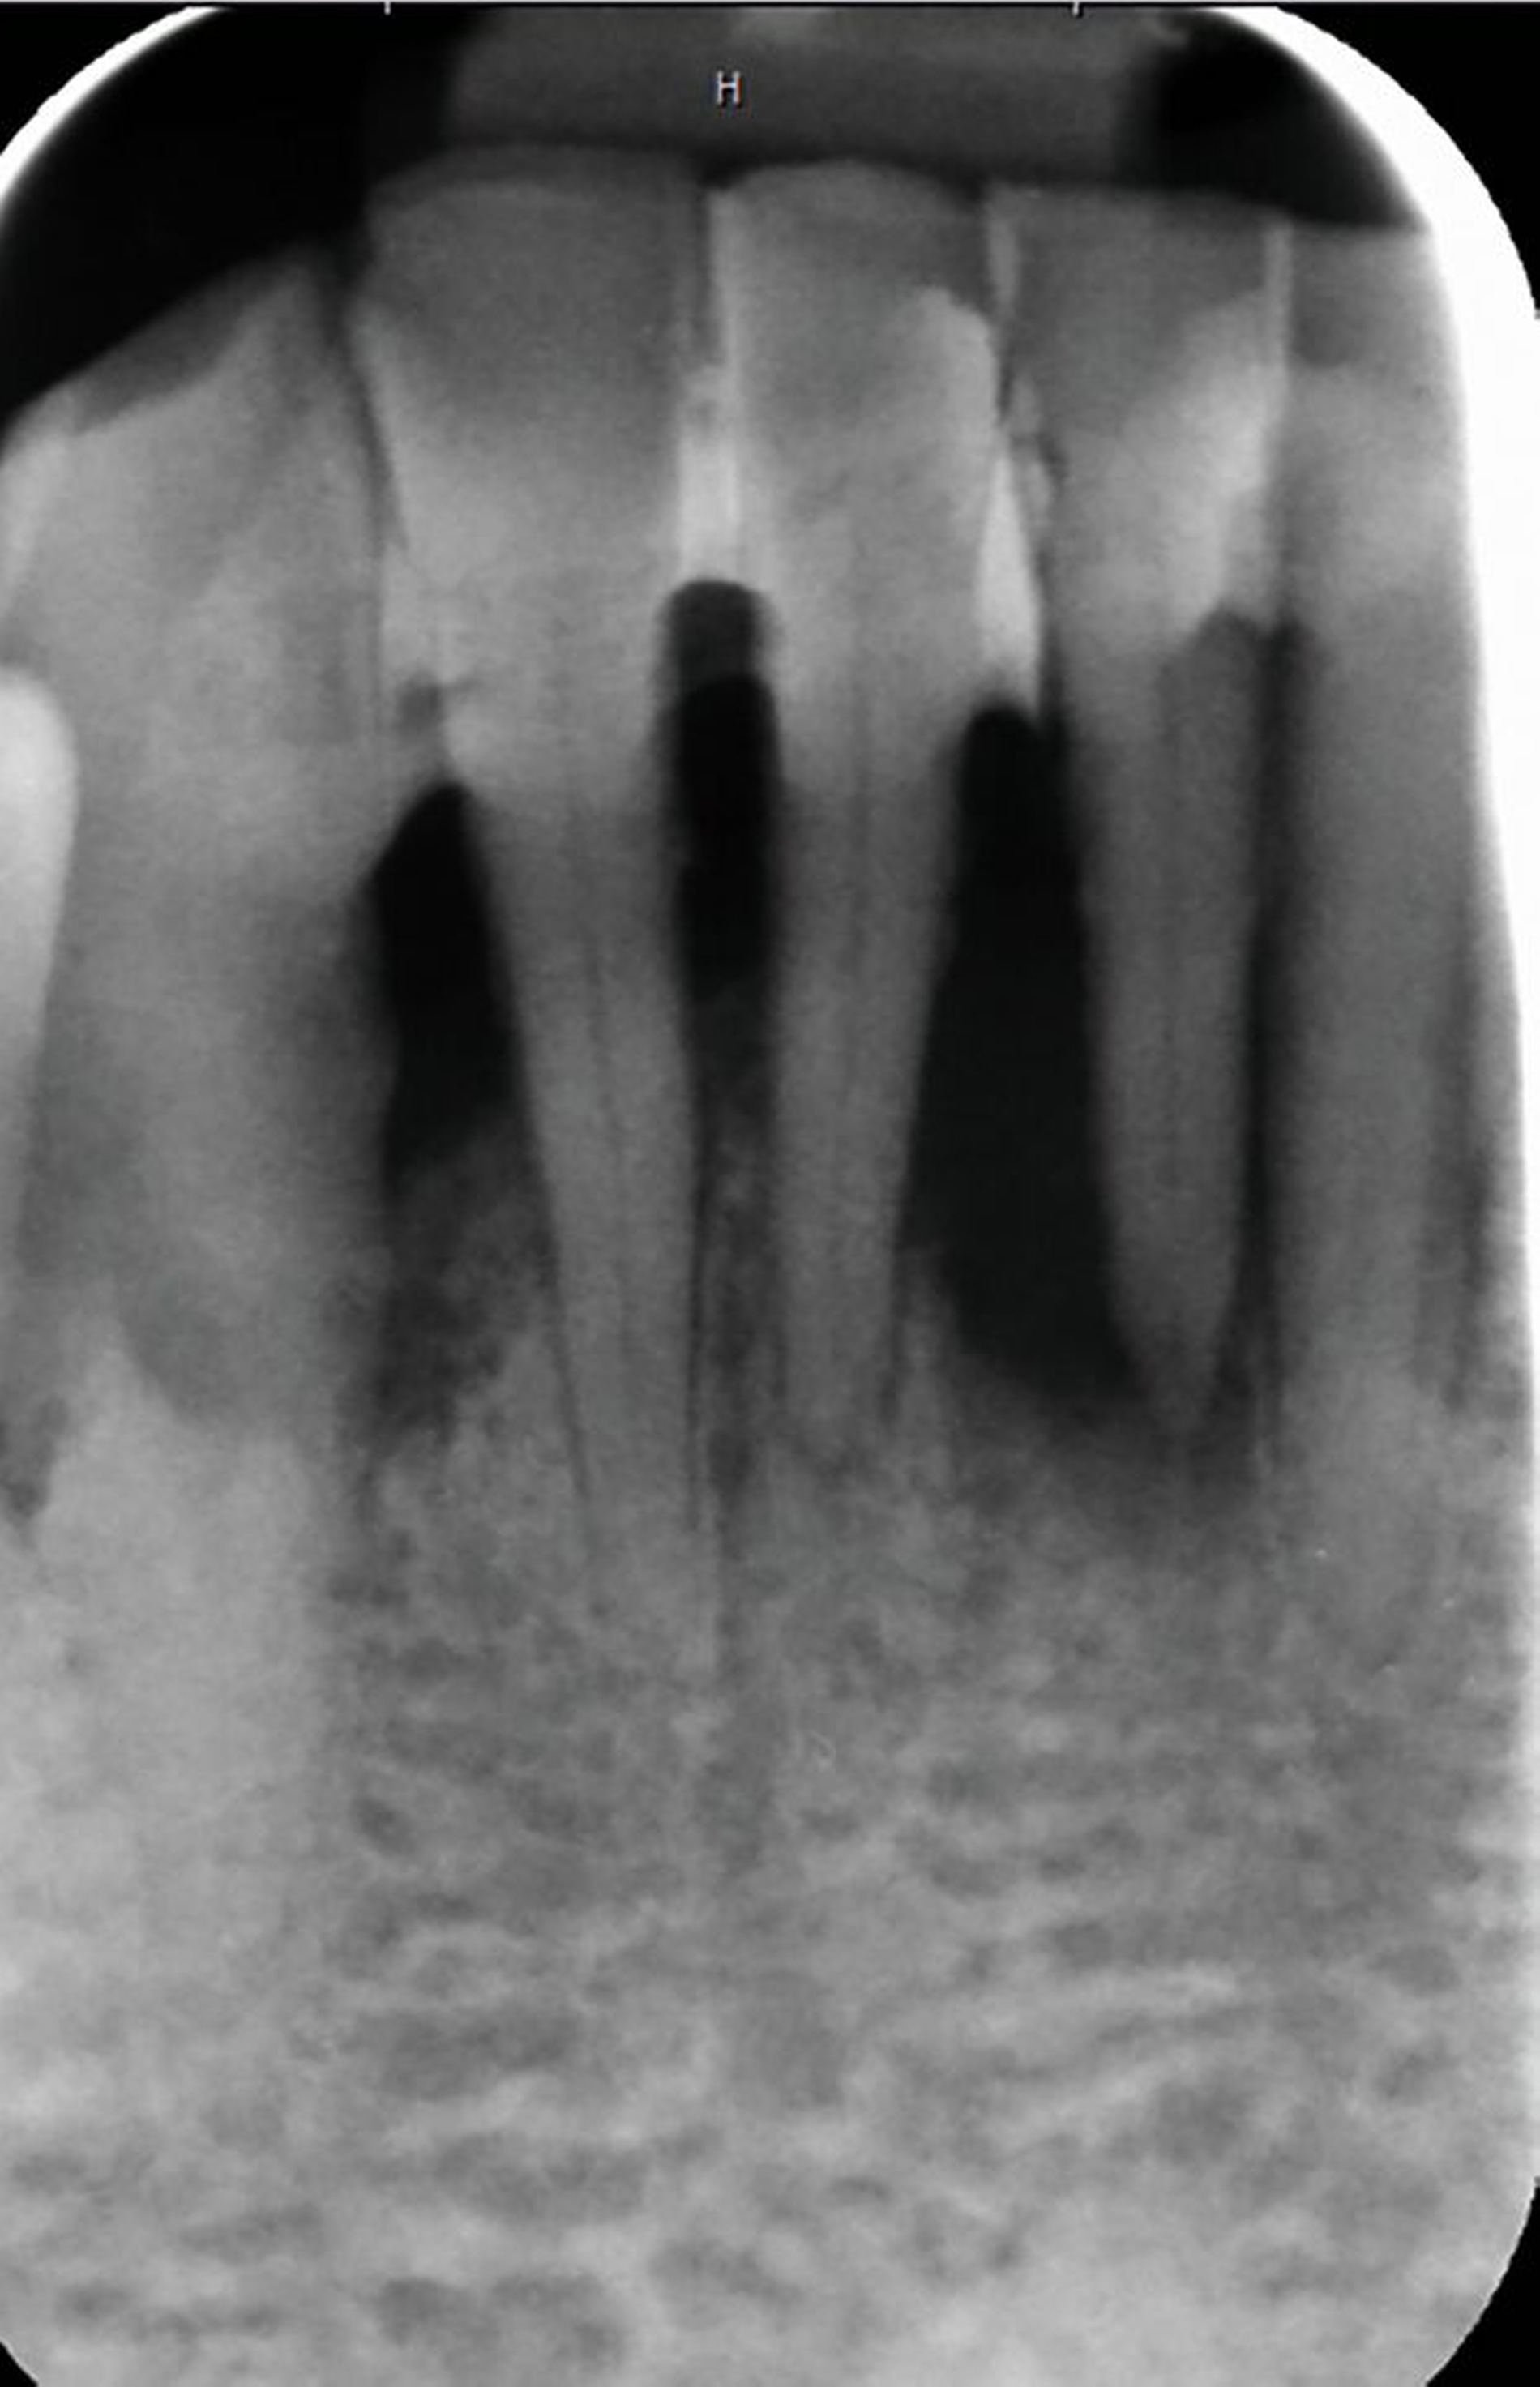

Die Herausforderungen der zahnmedizinischen Betreuung im höheren Lebensalter liegen außerhalb der Mundhöhle und haben nur indirekt etwas mit dem Alter zu tun. Im höheren Lebensalter steigt die Gefahr für Erkrankungen und Funktionseinschränkungen wie Gebrechlichkeit (Frailty), Demenz und Depressionen und/oder internistische sowie muskuloskelettale Erkrankungen. Diese Erkrankungen und Funktionseinschränkungen führen zu einer reduzierten Mundhygienefähigkeit der betroffenen Person. In der Folge kommt es besonders im vorgeschädigten Gebiss zu einer schnellen Progression kariöser oder parodontaler Erkrankungen. In Kombination mit organischen Funktionseinschränkungen wie zum Beispiel einer medikamenteninduzierten Xerostomie führt die Summation der Noxen – auch bei Personen, die ihre Mundgesundheit bis dato aufrechterhalten haben – zu oralen Komplikationen wie Zahnverlust und Entzündungen (Abbildung 1).